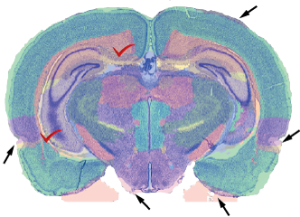

VisuAlign_illust.png